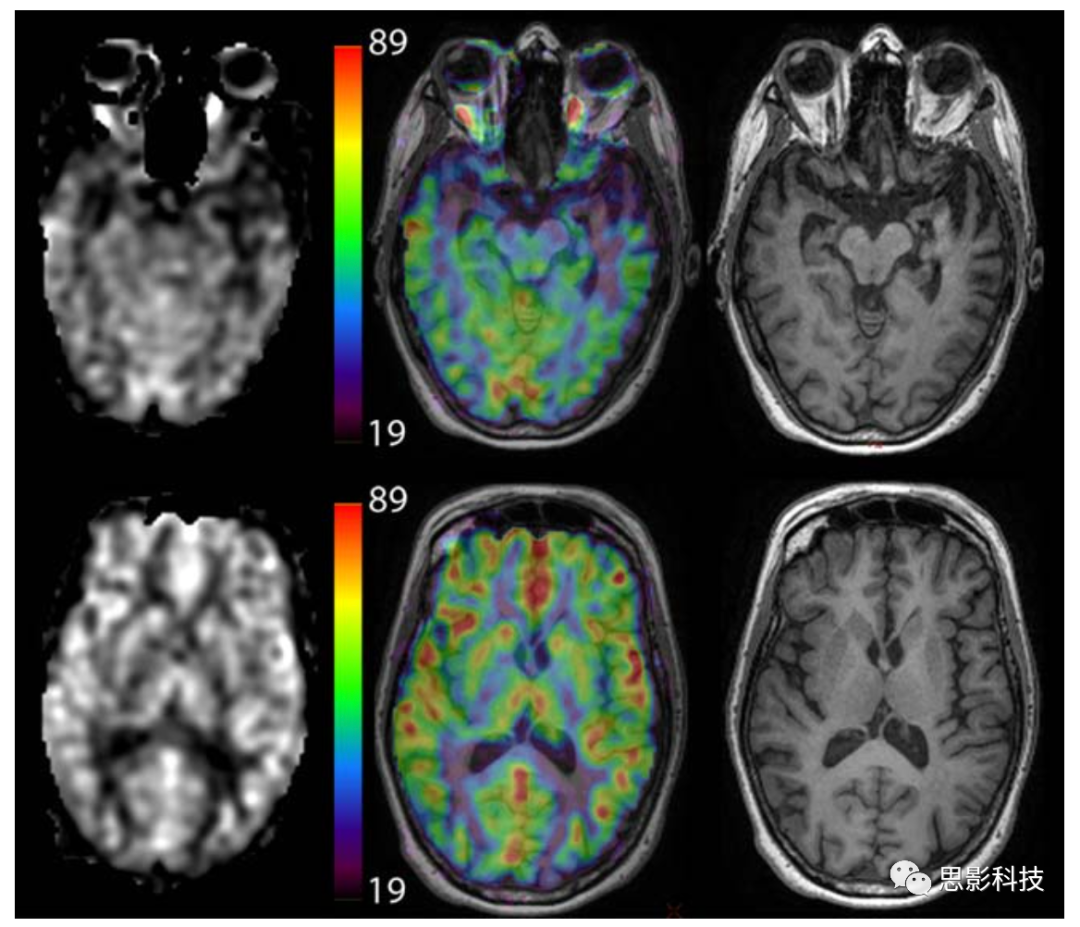

本文的目的在于为已有ASL灌注成像的临床应用提供补充意见,以提高数据的采集质量。ASL技术的发展至今已经20余年。ASL技术采集得到灌注影像质量已达到可用于临床以及研究应用的程度。但是经过多年的发展,有大量的标记方案以及各种模型实现脑血流(cerebral blood flow, CBF)的重建,这使得临床医生以及研究人员难以在各种方案中选择下最优的重建模型。使得构建各个部位的统计以及有意义的临床实验的建立变得复杂,这种广泛而无规范的实验操作减慢了在设备上应用ASL技术的速度,从而限制了该技术的推广。图1即为推荐参数下ASL扫描图像。

Figure 1 正常被试在推荐参数下asl扫描的图像

可视化

ASL技术的一个关键优势在于可得到绝对脑血流。本文建议采集人员以灰度或彩色查看生成的CBF图像,并在图像旁边使用定量比例尺指示CBF值(图8)。使用颜色可以提高从颜色棒读取定量CBF值的能力,但也可能导致错误的表观阈值,因此用户应注意这一潜在的陷阱。

Figure 8不同可视化方法的比较